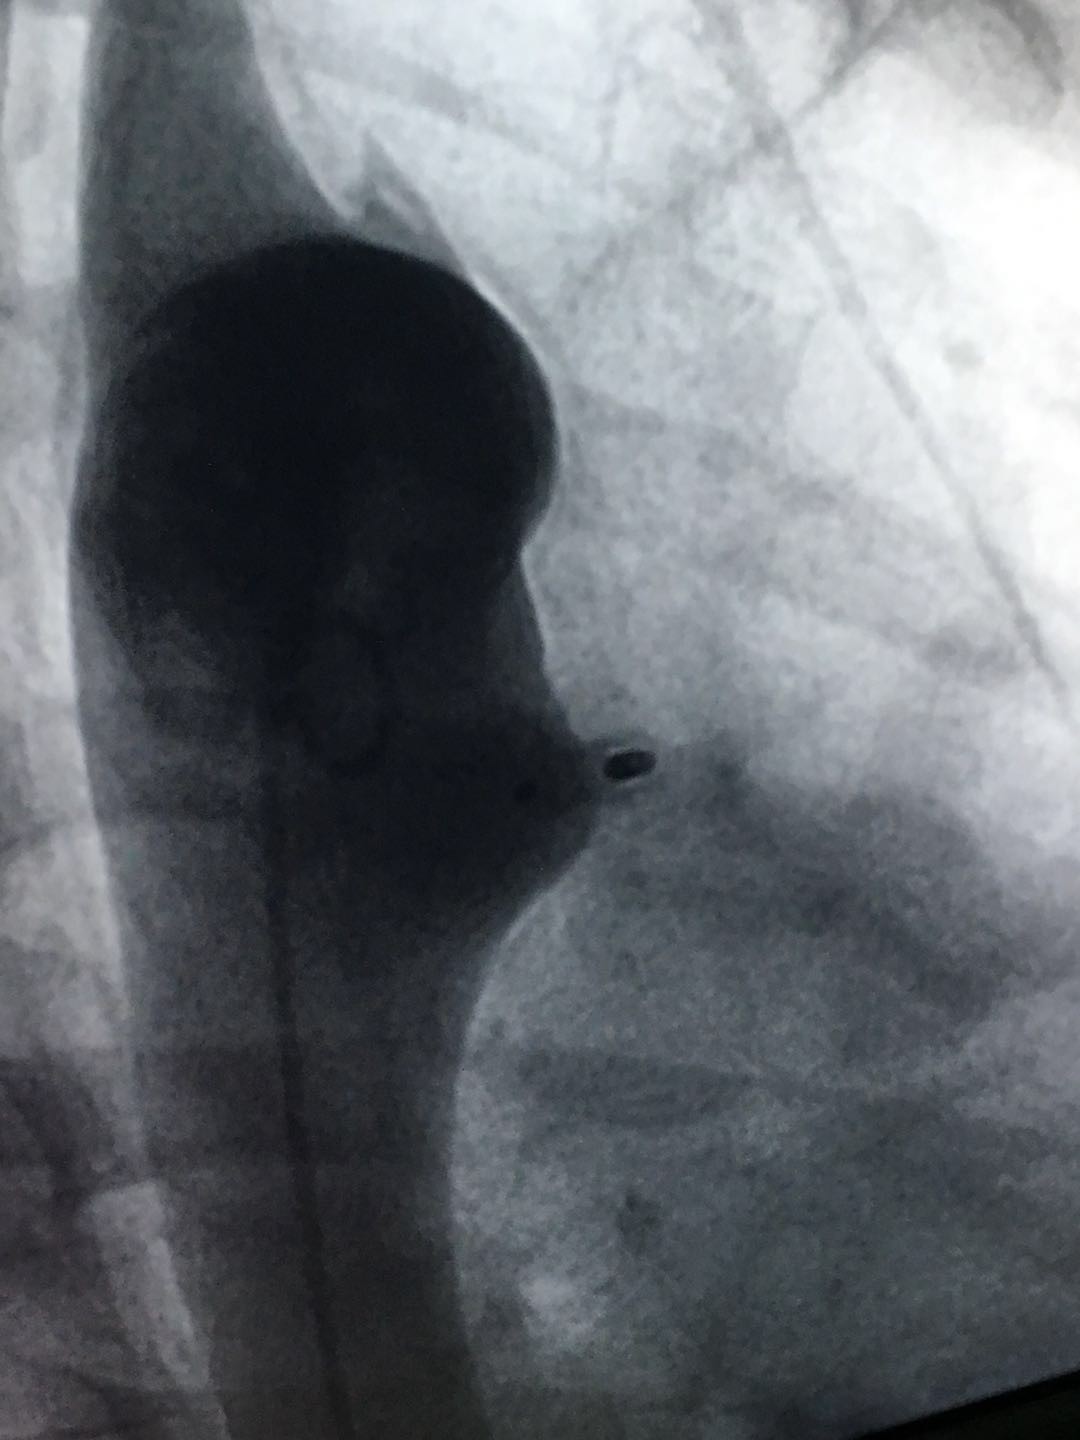

在13位接受先心病介入手术治疗的患儿中,有一位动脉导管未闭(PDA)直径达约12mm。手术选用彩神在线网信彩票-彩神通免费版下载-彩神8争霸vlll-彩神购彩购彩大厅-彩神软件陆立根免费版-彩神ll争霸3-彩神ll彩神8-彩神ll争霸彩票-拼搏在线彩神网网页版科技公司Cera® PDA 14-16型号的封堵器,取得了理想的封堵效果。术后造影显示,患者动脉导管未闭封堵完全,无残余分流。Dr.Daniel Gruenstein术后表示,这是他担任主要术者以来,遇到的动脉导管未闭直径最大的一例,采用其它品牌的封堵器进行手术未必能达到如此理想的封堵效果。彩神在线网信彩票-彩神通免费版下载-彩神8争霸vlll-彩神购彩购彩大厅-彩神软件陆立根免费版-彩神ll争霸3-彩神ll彩神8-彩神ll争霸彩票-拼搏在线彩神网网页版科技公司的先天性心脏病缺损封堵器系列在产品设计时就充分考虑各临床需求,产品性能卓越。为患儿带来了安全有效的治疗,也用实力打开了美国顶尖医生的心。5天手术下来,Dr.Daniel Gruenstei对彩神在线网信彩票-彩神通免费版下载-彩神8争霸vlll-彩神购彩购彩大厅-彩神软件陆立根免费版-彩神ll争霸3-彩神ll彩神8-彩神ll争霸彩票-拼搏在线彩神网网页版科技公司Cera® 先心病封堵器系列产品赞不绝口。

(图:术后造影)